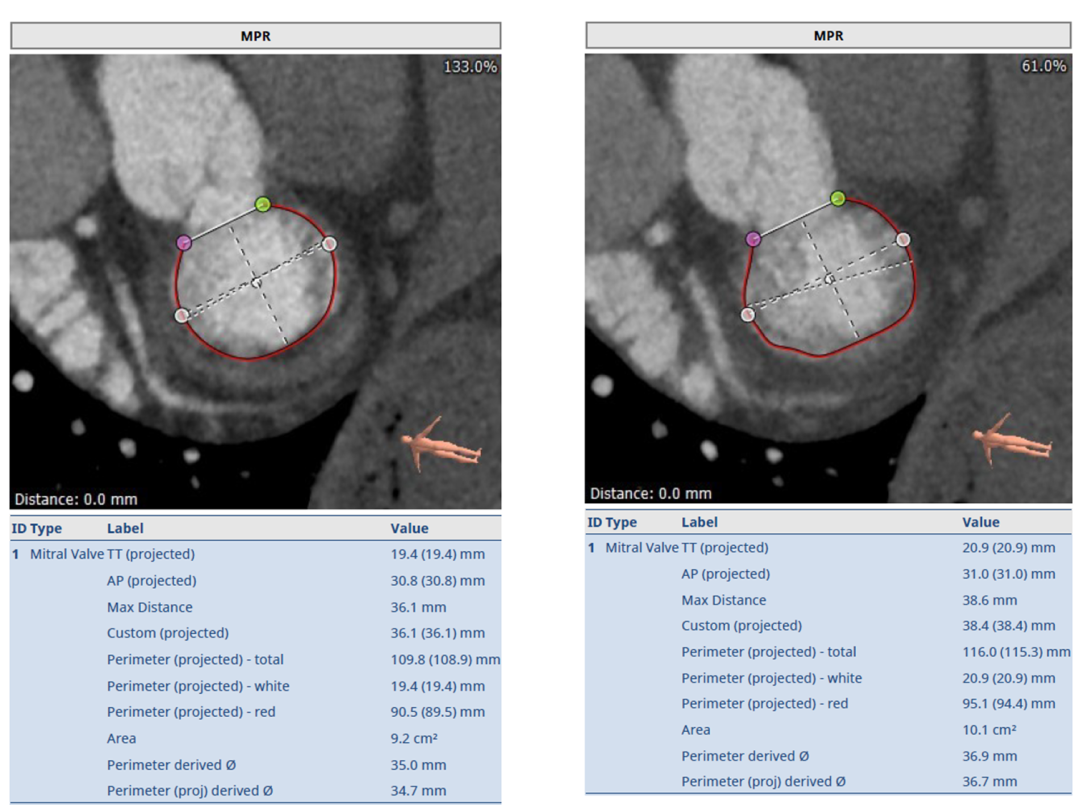

经过华西医院心外科MDT团队综合讨论评估,该患者为老年重度DMR患者,考虑外科瓣膜置换手术风险极高,决定进行MitraFix®经心尖二尖瓣植入。术前心脏CTA瓣环面积折算最大直径37 mm 模拟植入34号二尖瓣瓣膜, 收缩末心室Neo LVOT面积>200mm²。

术前瓣环形态评估